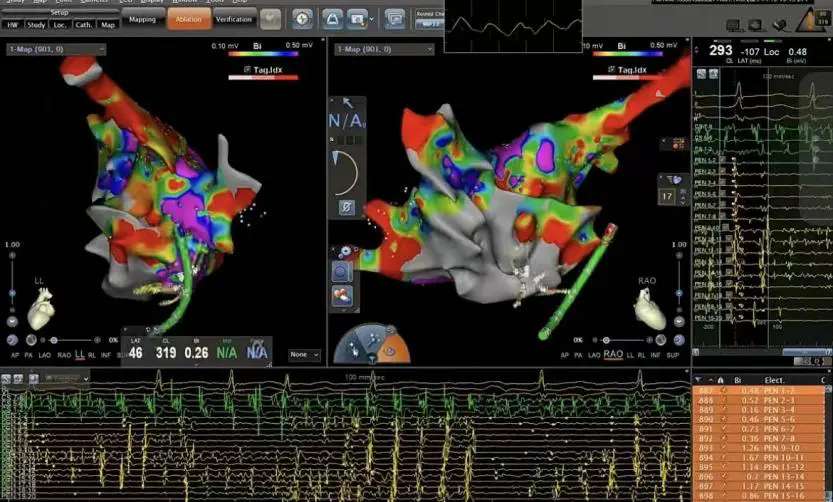

手术当天,在汕头大学医学院第一附属医院萧钟波教授精湛技术的指导下,我院心血管内科团队全神贯注,开始了这场与“心乱”的较量。心内电极导管在萧钟波教授的操控下,小心翼翼地在心脏内行进,修复着心脏的节律。医护人员紧盯监测仪器,密切关注着心脏电活动的变化。当最后一个颤动波在屏幕上消失,窦性心律稳定恢复的瞬间让所有人振奋——这标志着持续性房颤射频消融术获得成功!

此例手术成功的背后,是多学科协作的力量:超声科即时评估心脏结构;放射科辅助左房CTA(排除左心耳血栓);心血管内科医生团队优化抗凝、抗心律失常和降压方案,将风险降至最低;护理团队实施房颤专病护理常规,严格监测术后并发症,目前患者恢复良好,已顺利出院,后期随访患者心率恢复正常。